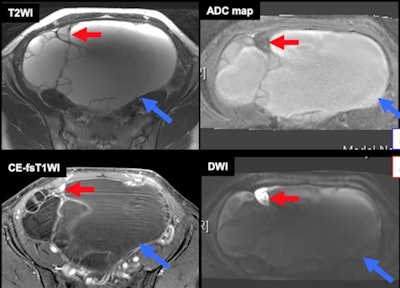

The definite imaging criteria includes the appearance of mural nodules; because T1-high hemorrhagic fluid may mask contrast enhancement of mural nodules, contrast-enhanced subtraction is useful. A malignant mural nodule shows high intensity on diffusion-weighted imaging (DWI) with a low apparent diffusion coefficient (ADC). Interval changes due to malignant transformation are dilution of hemorrhagic contents (disappearance of shading/T1-signal decrease) and interval enlargement of endometrioma.

"Clots in endometrioma may mimic malignant transformation," the authors wrote. "Contrast enhancement subtraction is critical for the differentiation. Susceptibility-weighted sequences may be also helpful in distinguishing clots from malignant transformation without administration of contrast medium, especially in patients with renal dysfunction, gadolinium allergy, asthma, or pregnancy."